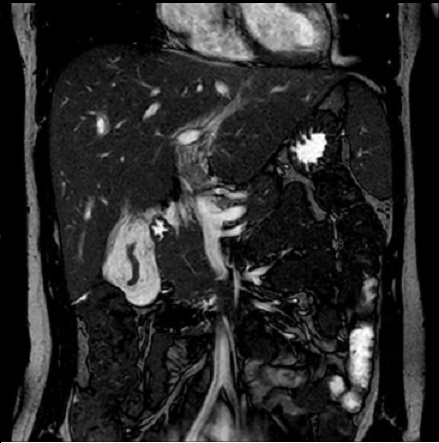

Image IRM de steatose fu foie

: Image de

hyperintense sur T1 et hypointense surT2 . L'infiltration graisseuse du foie provoque une diminution de

l'attenuation du parenchyme du foie . Sur le foie normale le

signal du parenchyme hepatique est similaire sur toutes les

images "in phase " et "opposed phase " . Dans steatose du

foie le signal du foie est hyperintense relative avec la rate (

T1 in phase ) et a opposed-phase , par la chute de

signal , image du foie est hypointensite ,

Steatose du foie : en phase .

Image IRM du foie |

|

Steatose du foie : Op de phase . |